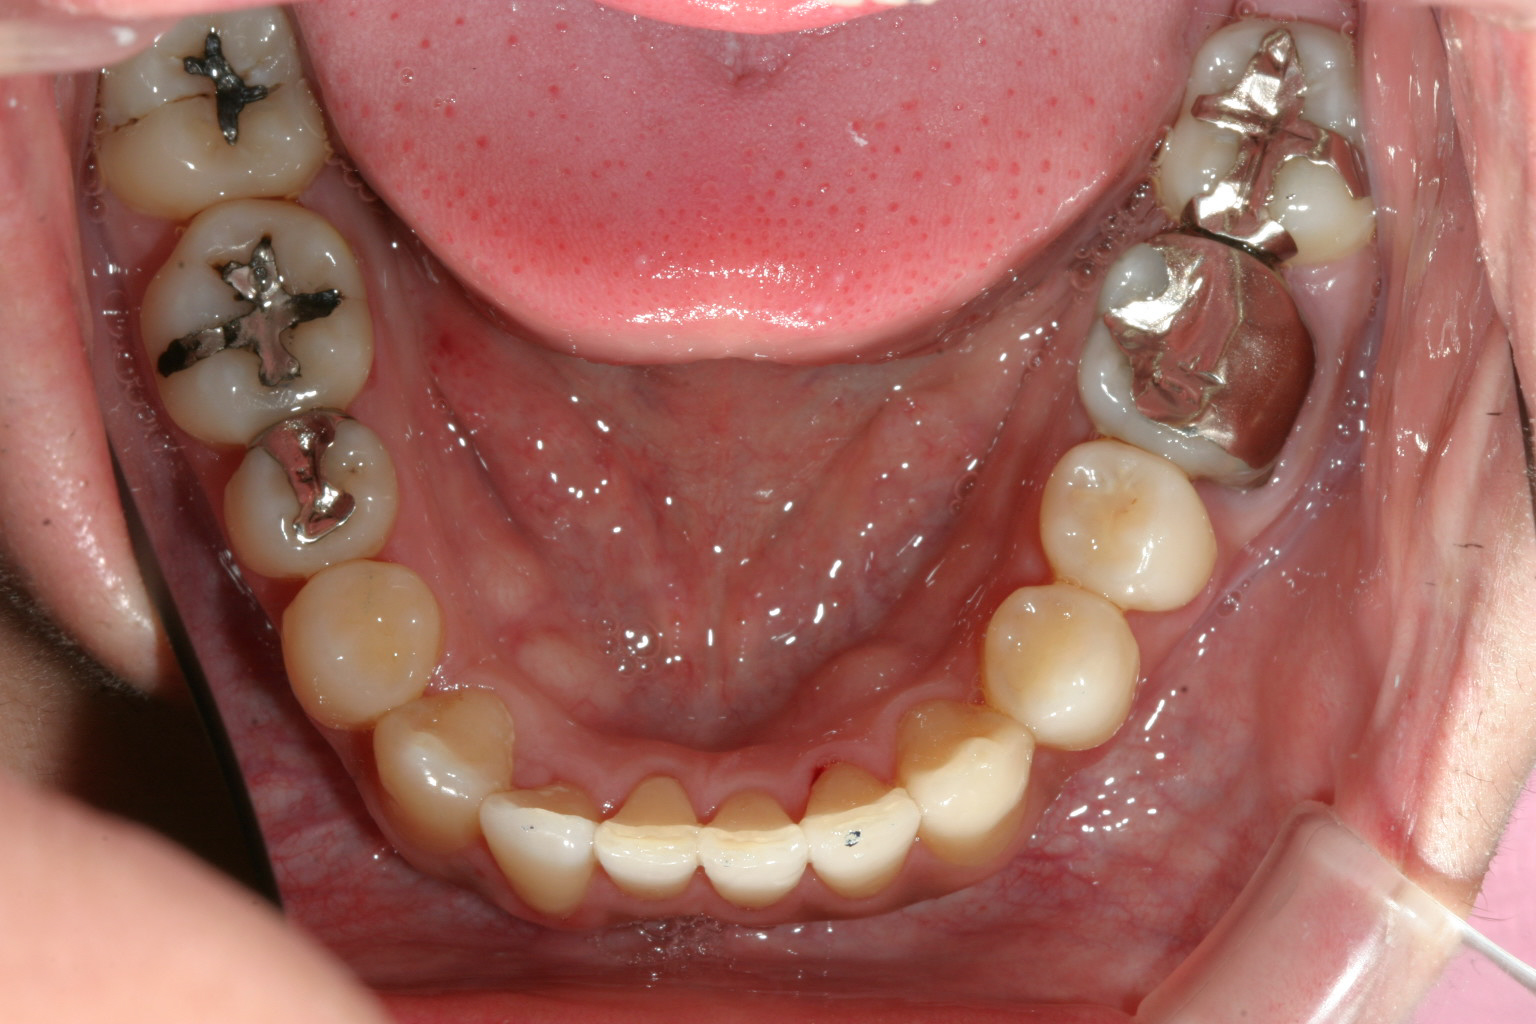

上顎がV字型の為下顎もV次型でその為叢生が存在します。

下顎も叢生も取れ綺麗に改善してます。